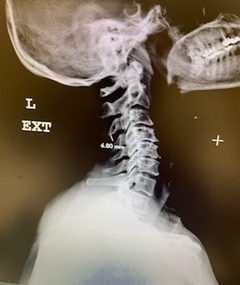

(2a) Lateral Flexion cervical x-rays demonstrating 8mm of splaying of the C34 interspinous distance

(2b) Lateral Flexion cervical x-rays extension image demonstrating 8mm of splaying of the C34 interspinous distance.

The fluid was possibly consistent with CSF versus chronic hematoma. The patient was also noted to have a high signal within the interspinous space of C3-C4. This high signal was consistent with a ruptured C3-4 interspinous ligament. Cervical flexion-extension x-rays demonstrated 6 mm of widening of the C3-4 interspinous space on flexion x-ray consistent with cervical instability (Fig. 2a and 2b).